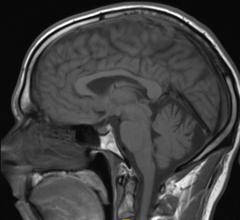

As one of the more precise methods of delivering radiation therapy for cancer treatment, proton therapy has grown at a rapid pace the last several years. Considered experimental not too long ago and used primarily in research settings, clinicians across the globe are rapidly coming to accept the utility of proton therapy for numerous indications — a list that many expect to continue to grow rapidly.

University Medical Center Groningen (UMCG) is one of the largest hospitals in the Netherlands. The hospital provides world-class patient care and is engaged in cutting-edge scientific research and medical education. UMCG is a leading cancer center and will soon open a new state-of-the-art proton therapy center.